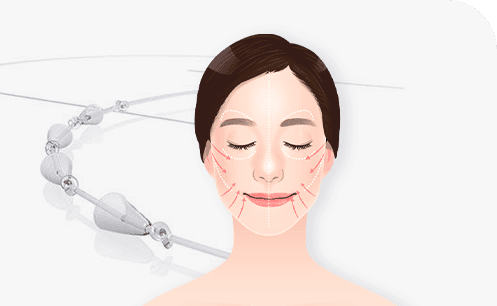

Thread Lifting

360° Clean Line

Technology, Principle, Core

Core Technology

Core technology and principles